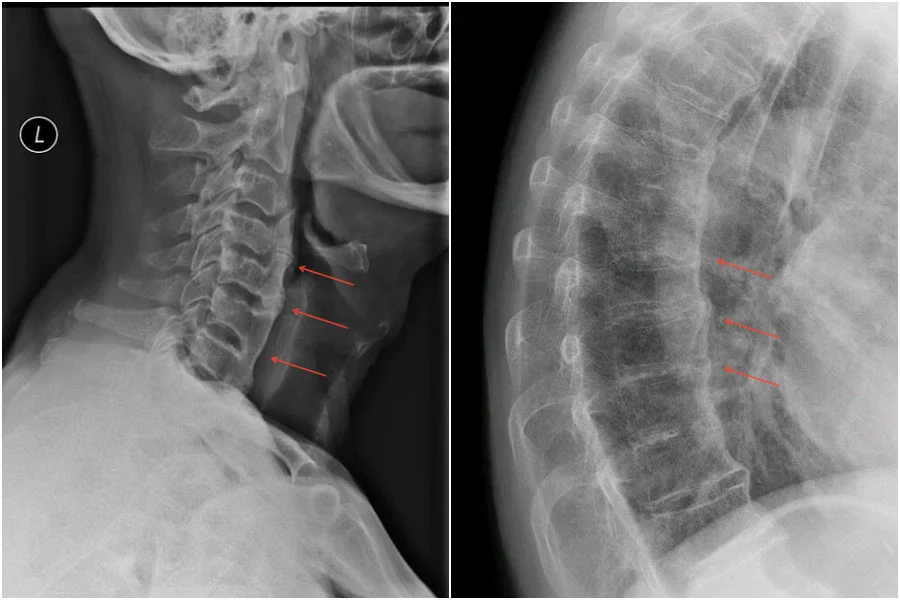

Рентгенография - Рентгеновите снимки на гръбначния стълб показват анормално костно образуване (осификация) по протежение на предния лигамент на гръбначния стълб. Дисковите пространства, фасетните и сакроилиачните стави остават незасегнати. Диагнозата изисква да е налице конфлуентна(сливаща) осификация на поне четири съседни прешлена. Класически, при напреднал процес, осификациите по протежение на гръбначния стълб има вид на „разтопен восък от свещ“. В някои случаи DISH синдром може да се прояви като осификация на ентезите или други части на скелета. Ентезите (местата на прикрепване на ставите или връзките към кост) често се калцифицират. Калцификацията и осификацията са най-често срещани от дясната страна на гръбначния стълб. При хора с декстрокардия и situs inversus тази калцификация се среща от лявата страна. Причините за това не са изяснени.

Изображения: Todorovic D, Diffuse idiopathic skeletal hyperostosis (DISH). Case study, Radiopaedia.org (Accessed on 09 Dec 2025); Jmarchn, CC BY-SA 3.0, via Wikimedia Commons